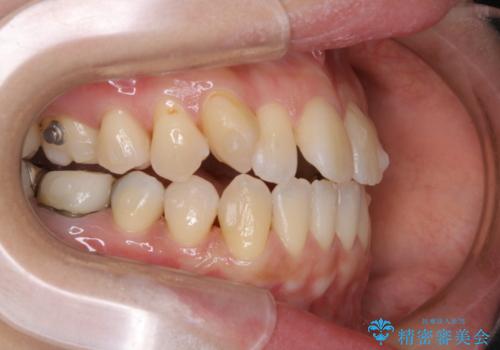

- インビザライン矯正治療中に頑固に付着した着色を取りたいとのことでした。PMTC60分コースを行いました。

矯正治療中もPMTCを定期的に行い、専門的な機械でしっかりと汚れを除去することがおススメです。

PMTCは30分コース・60分コースがあります。

30分コースでは主に前歯をメインに行います。

60分コースでは全体的に行います。